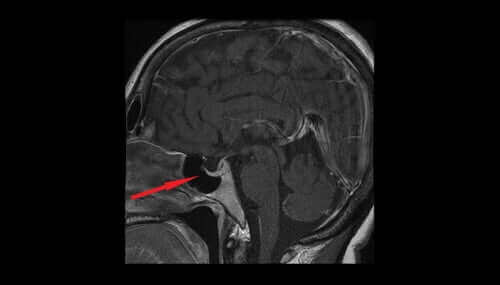

In dit artikel zullen we kijken naar de verschillende kenmerken en effecten van vasopressine. Vasopressine, ook bekend als antidiuretisch hormoon of ADH, komt uit de magnocellulaire kernen van de hypothalamus.

Van daaruit gaat het over naar de neurohypofyse en vervolgens uiteindelijk in het bloedsomloop. Het helpt de hoeveelheid water in het lichaam te reguleren door de hoeveelheid water die de nieren uitscheiden te regelen.

Het antidiuretisch hormoon dat vrijkomt uit hypothalamische neuronen heeft met de regulering van bloeddruk en temperatuur te maken. Er zijn aanwijzingen dat dit hormoon pijnstillende effecten kan hebben, die van seks en stress afhankelijk zijn.

Lage niveaus van het antidiuretisch hormoon zorgen ervoor dat de nieren overtollig water uitscheiden. Het urinevolume zal toenemen en zal tot uitdroging en een verlaging van de bloeddruk leiden. Lage niveaus van het antidiuretische hormoon kunnen dus op schade aan de hypothalamus of hypofyse of primaire polydipsie duiden.